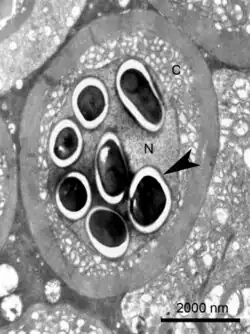

Transmission electron micrograph of an Enterospora nucleophila-infected rodlet cell harbouring spores within its nucleus (N). No stages are visible in the cytoplasm (C)

Enterospora nucleophila is a microsporidian infecting the gilt-head bream (Sparus aurata). It develops primarily within the nuclei of rodlet cells and enterocytes, at the intestinal epithelium. It can also be found in cytoplasmic position within other cell types, including phagocytes, at subepithelial layers. It is the causative agent of emaciative microsporidiosis of gilthead sea bream, a chronic condition manifested as a severe growth arrestment, normally accompanied by trickling mortality.